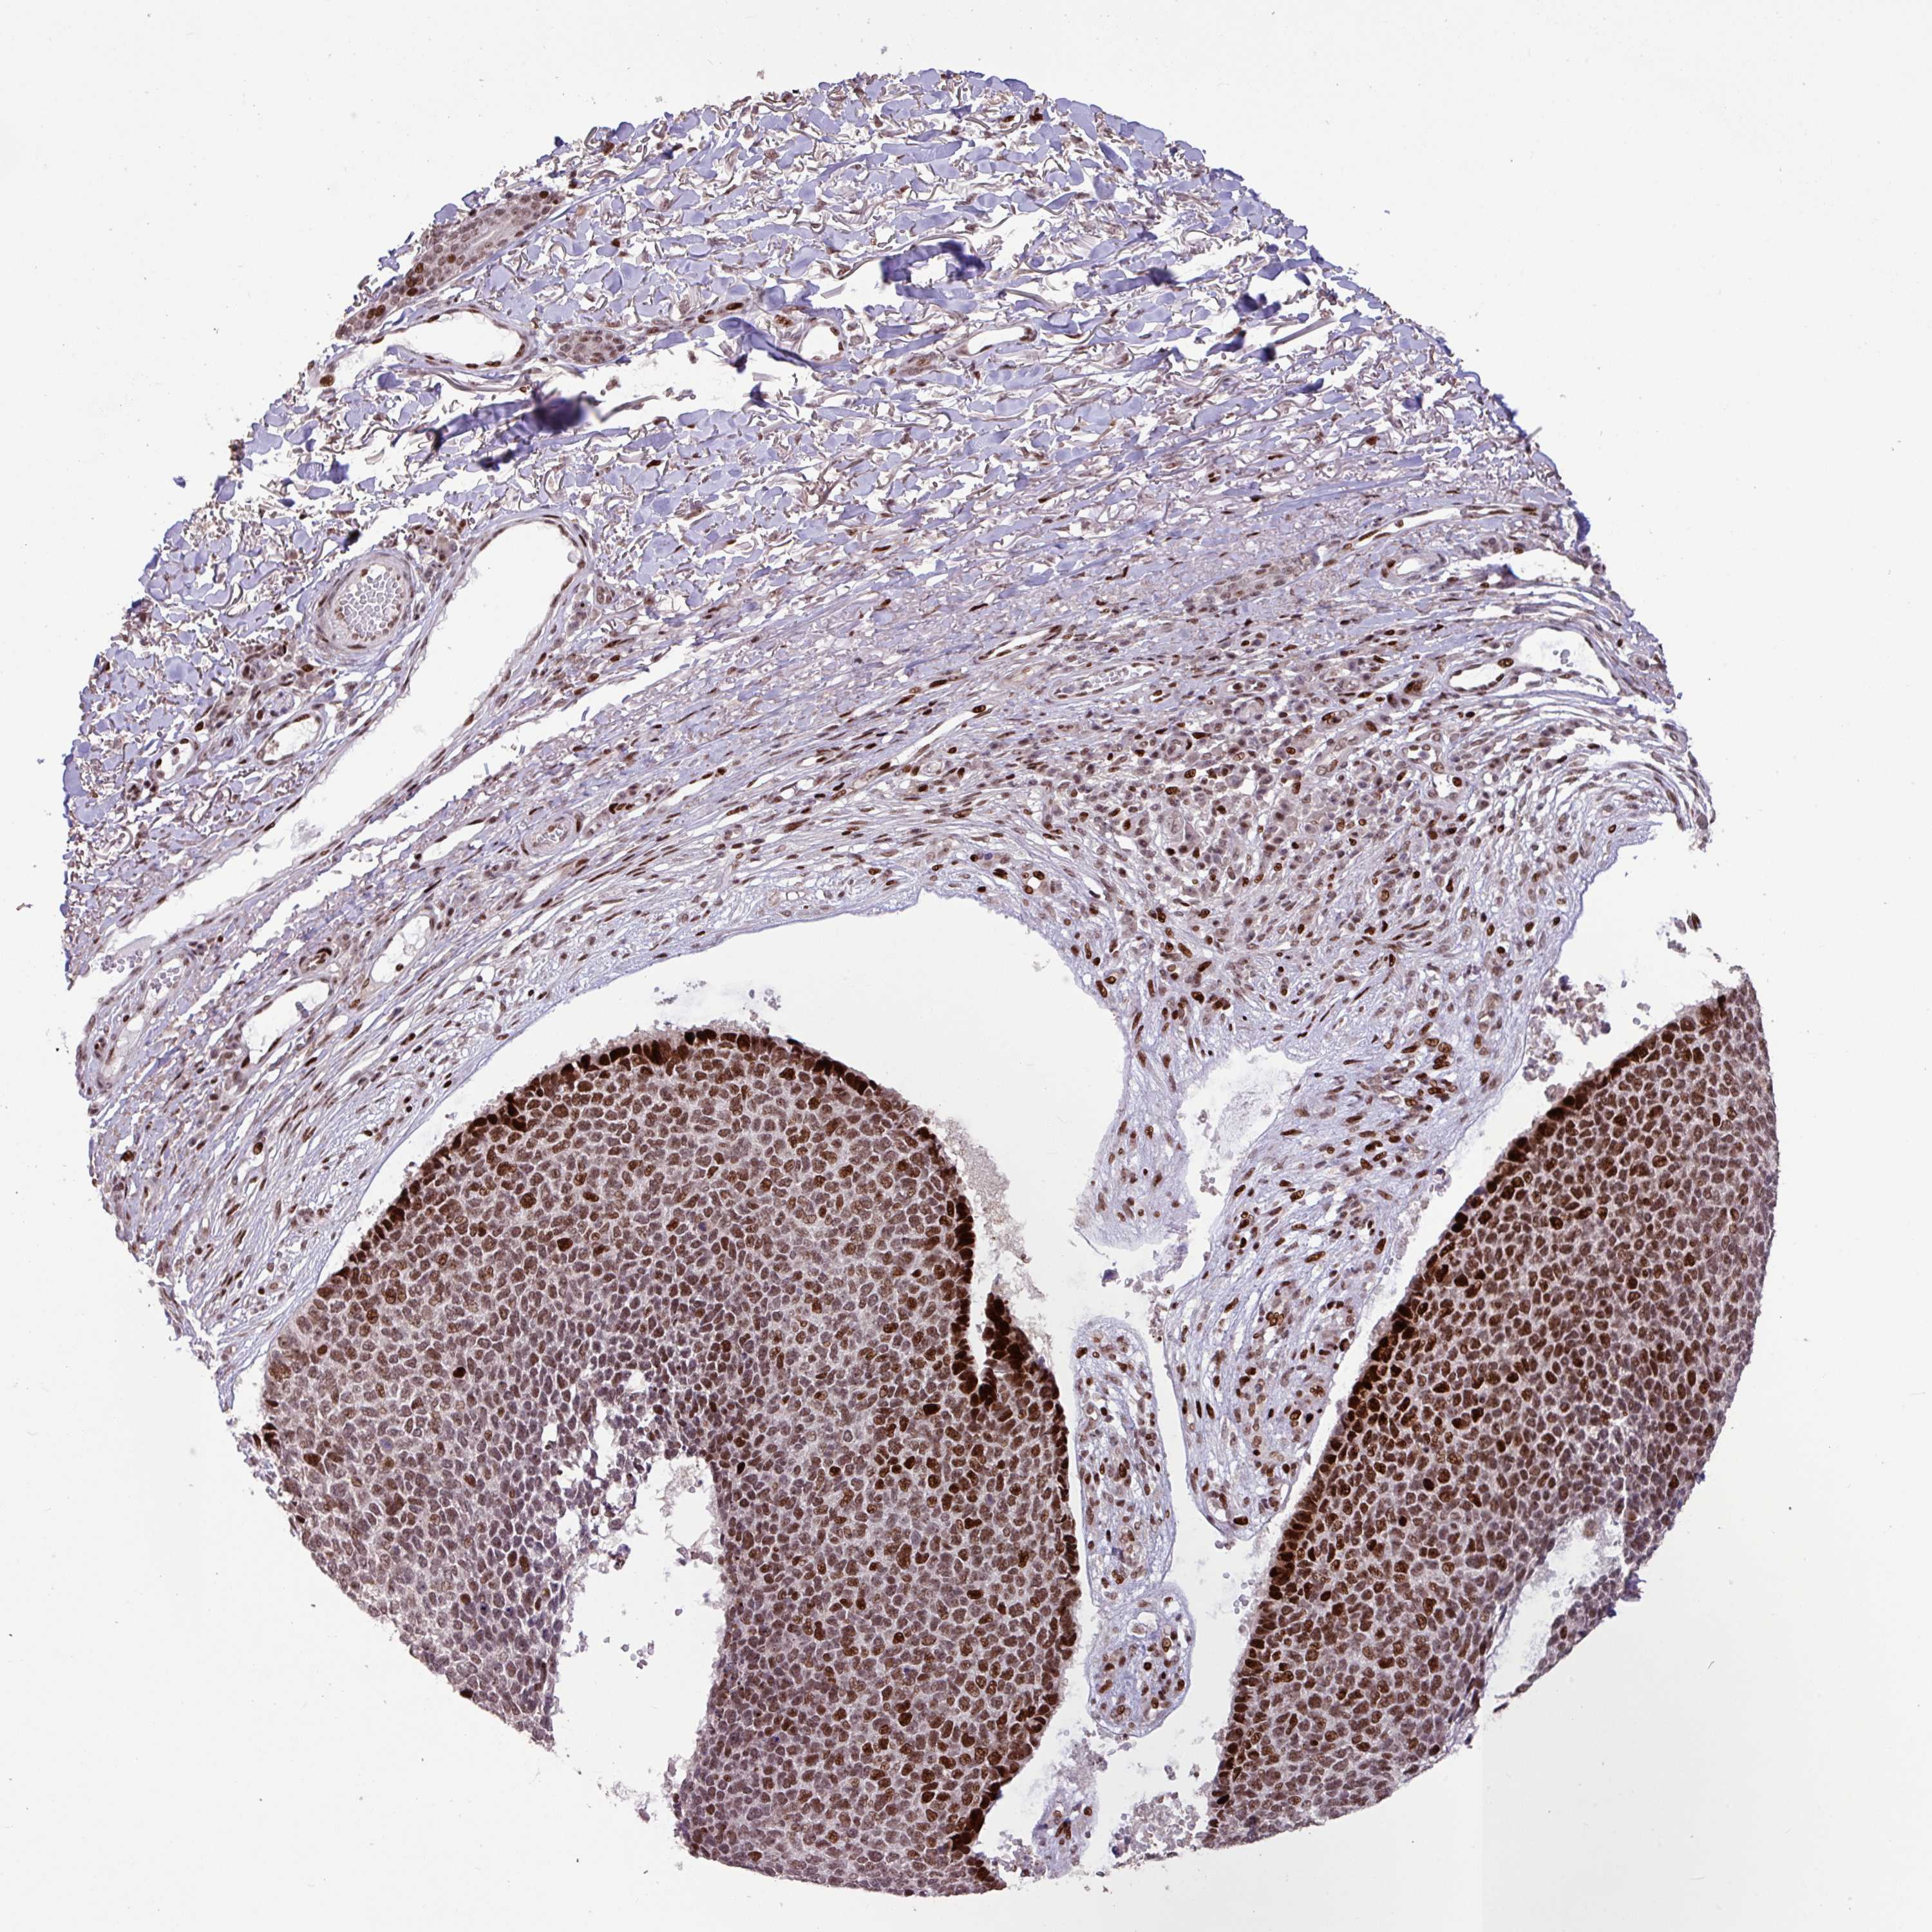

Basal cell and squamous cell cancer

SKIN CANCER - Protein expressioni

A mouse-over function shows sample information and annotation data. Click on an image to view it in a full screen mode. Samples can be filtered based on level of antibody staining by selecting one or several of the following categories: high, medium, low and not detected. The assay and annotation is described here.

Antibody HPA053153

Squamous cell carcinoma, metastatic, NOS